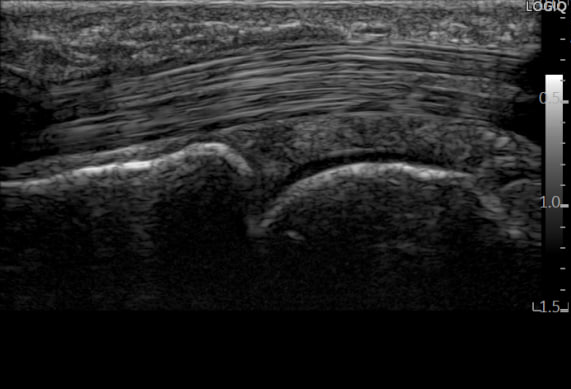

자세한 상태를 진단하기 위해

경혈 초음파로 검사해보았습니다.

경혈 초음파로

침 놓을 혈자리를 살펴보니

A1 도르래가두꺼워진 상태였습니다.

정밀하게 체크해보니

힘줄 주변 집도

어둡게 부어있고

A1 도르래(활차)에

물혹(결절종)도 확인되었습니다.